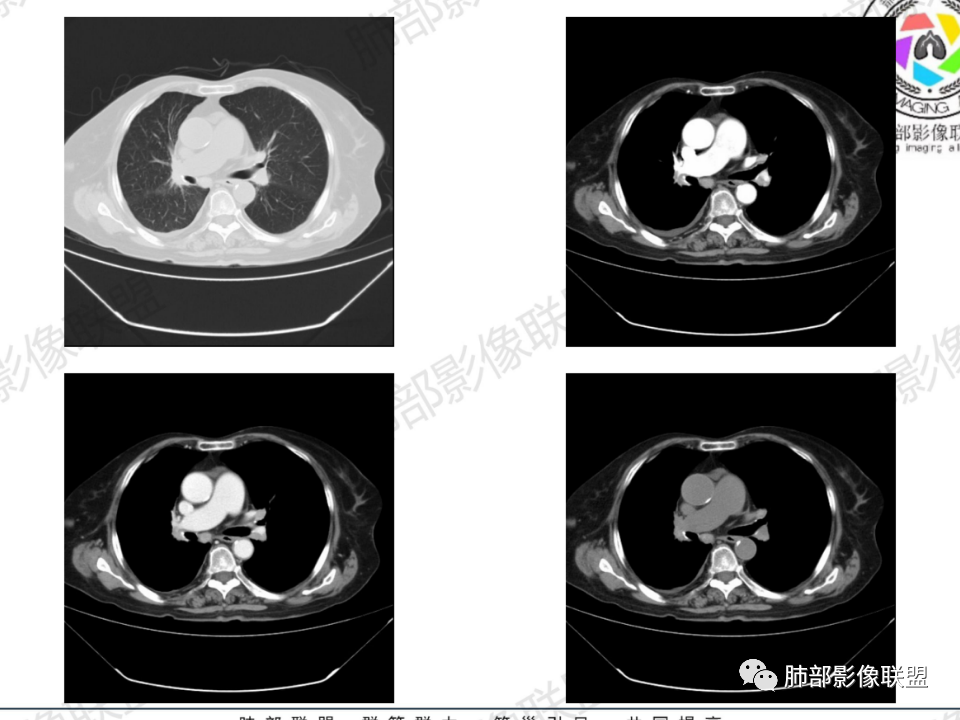

老年患者,病程中等,有咳嗽/喘息/低热症状,肿瘤标志物升高,感染标志物不高,右上肺新生物,中央型,边界清楚,有分叶,支气管截断,内有坏死,不均匀强化,考虑肺癌,鳞癌?

那个人:老年女性,亚急性病程,咳嗽发热。有垂体前叶功能减退,目前激素替代治疗,长期激素,量小,不知道累积量,没有目前激素水平指标。既往有淋巴结结核病史。肿瘤标记物Ca125升高。血沉升高,C反应蛋白轻度异常。影像,右肺上叶靠近肺门团块影,右肺门淋巴结钙化肿大,支气管狭窄,局部增厚,团块影外朝内改变,强化明显,血管破坏不明显,有粘液。和纵隔胸膜分界清楚,周围肺组织有斑片渗出影,右侧胸腔积液,考虑炎性?结核?支气管镜检查除外恶性飞鹰行动:老年患者,影像表现 右肺上叶占位性病变,边界清楚,有分叶征,内见细小钙化,右肺上叶支气管截断,增强病灶不均匀强化,病灶内有条状坏死区(扩张的支气管?),纵膈内未见增大淋巴结,考虑炎性病变,结核可能。一切∮随缘:右肺上叶实性肿块形态不规则,呈三角形,边缘分叶,边界伴有磨玻璃影,近段支气管未见明显显示,可能堵塞,病变平扫密度均匀,增强后可见低密度坏死无强化,周围略强化,右肺下叶散在结节。心包积液,及右侧胸腔积液,临床:有低热,低蛋白血症,肿瘤标记物高,考虑恶性:腺癌,神经内分泌癌(强化偏弱了),淋巴瘤,鉴别:结核红星:老年女性患者右肺上叶,肺门上区 分叶状肿块 ,右肺上叶支气管显示不清,增强扫描肿块,中等程度强化可见小斑片状坏死区,病灶内部可见斑点状钙化灶,病灶周围可见斑片状及小斑点状影,纵膈淋巴结增大,其他区域,胸膜下可见斑点状钙化。考虑肉芽肿性病变,结核的可能性大。老年患者最排除肿瘤性病变腺癌。土娃:右上肺不规则肿块影,边缘分叶,边界磨玻璃影欠清,病灶分叉状,内见点状钙化影及坏死灶,支气管堵塞,病灶增强强化不明显。考虑瘤样结核,鉴别淋巴瘤。张小兵:老年女性,亚急性病程,右肺上叶见不规则肿块,边缘平直凹陷为主,周围GGO边界不清,内见点状钙化及坏死灶,增强持续性渐进强化,右侧少量胸腔积液,双肺门及纵隔肿大淋巴结伴钙化,综合考虑慢性炎症。saf:老年患者,影像表现 右肺上叶占位性病变,边界清楚,有分叶征,增强病灶明显不均匀强化,纵膈内未见增大淋巴结,考虑炎性病变,结核可能。小兜:老年女性,咳嗽喘息一月,发热三天,肿瘤标志物升高,长期激素替代治疗。CT示右肺上叶近肺门不规则实变影,周围伴磨玻璃影,增强持续性渐进强化,内部血管破坏不厉害,内部可见多发条形低密度灶,右侧胸腔可见少量积液,双肺门及纵隔可见钙化淋巴结,考虑为炎性病变,结核可能玫:女,79咳嗽,喘息一月,发热三天入院,右肺上叶不规则形软组织密度肿块影,边界清晰,边缘见分叶及细短毛刺,病灶内见点状钙化影及稍低密度区,病灶边缘呈磨玻璃样改变,增强扫描,病灶呈不均匀性强化,考虑炎性病变,鉴别鳞癌。大雄:老年女性,既往诊断淋巴结结核,提示已治愈,近2年服用激素,诱导结核复燃→发热;纵隔肺门淋巴结肿大钙化,压迫支气管,右肺上中下叶支气管均狭窄→喘息咳嗽;尖段支气管受累闭塞→肺不张、支气管粘液栓;累及胸膜,结核性胸膜炎并胸水→右侧胸痛;实验室,血沉快,CA125高,低蛋白,符合;下一步,支气管镜尖段支气管刷检抗酸染色周太狼:老年女性,亚急性病程,肿瘤标志物升高。CT示右肺上叶尖段不规则肿块影,有分叶、收缩,周围伴磨玻璃影,增强渐进强化,内部可见多发条形低密度灶,右侧胸腔及心包少量积液,纵隔内淋巴结稍增大。倾向于恶性病变,肺癌伴阻塞性炎变可能。丽:老年女性,右肺上叶不规则软组织肿块,边缘清晰,内密度不均,可见点状钙化及粘液栓,周围可见片状高密度影,增强后均匀强化,内多发低密度,纵膈多发钙化淋巴结,考虑结核可能大,建议结合支气管镜检查除外肿瘤宇宙:右胸廓缩小,右肺上叶团块影及不张,平直边,周围磨玻璃影,纤细胸膜牵拉,上叶尖段支气管堵塞,明显延迟强化,可见支气管粘液栓,两肺门钙化淋巴结,右侧胸水,考性炎性肉芽肿,鉴别腺癌王秀仙:右肺上叶肺门区肿块,上叶支气管开口阻塞,形态不规则,密度不均,内可见支气管粘液栓及多发小灶性坏死,周围磨玻璃影边缘模糊,渐进强化,右侧胸腔积液、胸膜钙化,考虑炎性肉芽肿性病变,慢性炎症。鉴别鳞癌,结核。刘丹:老年女性,右肺上叶肿块伴钙化,右肺上叶支气管截断,增强后均匀强化,周边可见点片状模糊影,右侧胸腔积液,右肺门淋巴结增大,考虑占位并阻塞性炎症,肿瘤?结核?建议纤支镜检查。小飞:右肺上叶纵隔旁软组织肿块,边缘深分叶、长毛刺及毛刷样短毛刺,边缘磨玻璃影,磨玻璃边界模糊,支气管截断,平扫密度不均,可见点状钙化,增强不均匀明显强化,心影增大,心包积液,右侧胸腔积液,考虑恶性肿瘤,腺癌?秦化君:右肺上叶不规则分叶软组织密度肿块,边缘清晰,胸膜牵拉,周围花花草草,上叶尖段支气管阻塞,内可见点状钙化,增强后密度不均可见支气管粘液栓及坏死区,内见血管分枝。中间段及中叶,下叶支气管狭窄,壁见钙化。右肺门淋巴结肿大,右侧胸腔积液,心包粘连肥厚。考虑1右上肺恶性病变,鳞癌?2右肺多叶段支气管狭窄,考虑支气管内膜结核?3胸腔积液及肺门淋巴结肿大,转移?风儿:老年女性,右肺上叶肿块,形态不规则,外围大内带小,边缘分叶膨隆平直及毛糙,密度不均,内见支气管粘液栓及多发小灶性坏死,坏死边缘清晰 ,渐进强化,上叶尖段支气管阻塞,叶支气管壁有局限性增厚,邻近胸膜腔微积液;纵隔及双肺门淋巴结肿大,部分钙化,右侧胸腔积液、心包积液、胸膜钙化,考虑炎性,肉芽肿性结核可能性大。鉴别鳞癌,女性及血供均不支持;腺癌,坏死边界太清晰。流心明智:老年女性,79岁,咳嗽、气短1月,发热3天。胸CT:右肺上叶见不规则肿块,边缘有膨隆、有平直凹陷,周围GGO边界不清,病灶内见点状钙化、粘液栓,尖段支气管未见,增强持续性渐进强化,右侧少量胸腔积液,双肺门及纵隔肿大淋巴结伴钙化,肺动脉增粗。考虑:右上叶尖段堵塞并慢性炎症,支气管TB并结石?鉴别Ca

右肺体积小,提示既往结核

支气管影

前,后段都在,没有堵塞

支气管壁增厚,周围磨玻璃边界不清,提示炎症。胸膜下钙化符合结核

近期发热符合感染

这个层面往上应该是尖段,显示不清

背段支气管周围增厚伴钙化,符合结核改变

胸腔积液并胸膜钙化,符合结核;

结核是肯定有。现在最大问题是尖段

近端显示不清,但是远端是粘液栓,可以认为是还行的

如果是近端鳞癌,远端应该会堵塞,不会整个肿块里面还有较为通畅的支气管

这个区域我们看到密度与周围一致,并不是肺癌伴周围不张的感觉,所以鳞癌暂时是不支持的

临床信息:老年女性,亚急性病程,咳嗽发热。有激素使用史。既往有淋巴结结核病史。肿瘤标记物Ca125升高。血沉升高,C反应蛋白轻度异常。 影像所见:右侧胸廓相对狭小,右肺上叶不规则团块影贴附纵隔旁,轻度分叶,整体密度较均匀,偶见钙点。

相应上叶尖端及前段支气管开口未能追踪(阻塞),开口处见钙化。病灶渐进性强化,并衬托出较完整尖段及前段含液支气管影。支气管开口区域未见异常高密度强化(如类癌等)及相对乏血供区(如鳞癌)。病灶区未见液化坏死。右上纵隔及胸廓入口区未见病灶胸膜外突破(栽赃)。

右肺上叶后段等区域散在片状影,边界不清(提示渗出性病灶)。

纵隔及双肺门见钙化淋巴结。心包积液,右侧胸腔积液(提示存在活动新病灶)。双侧胸膜下见多发斑点状钙化,胸廓变形(提示存在结核基础病变可能)。 诊断意见:综上,右肺上叶块状影更符合继发性肺结核。 最后小结:既往诊断淋巴结结核,提示已治愈。近2年服用激素,可疑诱导结核复燃,也可引起发热。纵隔肺门淋巴结肿大钙化,压迫支气管,右肺上中下叶支气管均狭窄,所以引起喘息咳嗽。尖段支气管受累闭塞,导致肺不张、支气管粘液栓,出现条状无强化区。病变累及胸膜,导致结核性胸膜炎并胸水,引起右侧胸痛。实验室检查血沉快,CA125高,低蛋白,均符合结核。下一步,建议支气管镜尖段支气管刷检并抗酸染色。(本段摘自於雄老师精彩发言)